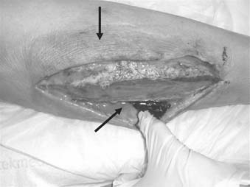

Over the course of the next 3 weeks of her hospitalization, H. S. underwent three serial surgeries, which involved extensive circumferential, bilateral lower extremity debridements, complex closures of the wounds, split-thickness skin grafting, and wound V. A. C. application. A peripherally inserted central catheter was placed to administer intravenous antibiotics (see Figures 1-3).

Figure 1 - Click to enlarge in new windowFigure 1. H. S.'s left medial calf prior to debridement in the operating room. Note the skin changes circumferentially around the wound and purulence along the facial plane. Photograph courtesy of Loren Schechter, MD, FACS, Division Director, Plastic Surgery, Advocate Lutheran General Hospital.

Figure 2 - Click to enlarge in new windowFigure 2. H. S.'s bilateral lower extremities and wounds prior to further debridement in the operating room. This was subsequent to a previous debridement. Note the necrotic changes along the anterior aspect of the skin margins and the extensive amount of debridement. Photograph courtesy of Loren Schechter, MD, FACS, Division Director, Plastic Surgery, Advocate Lutheran General Hospital.